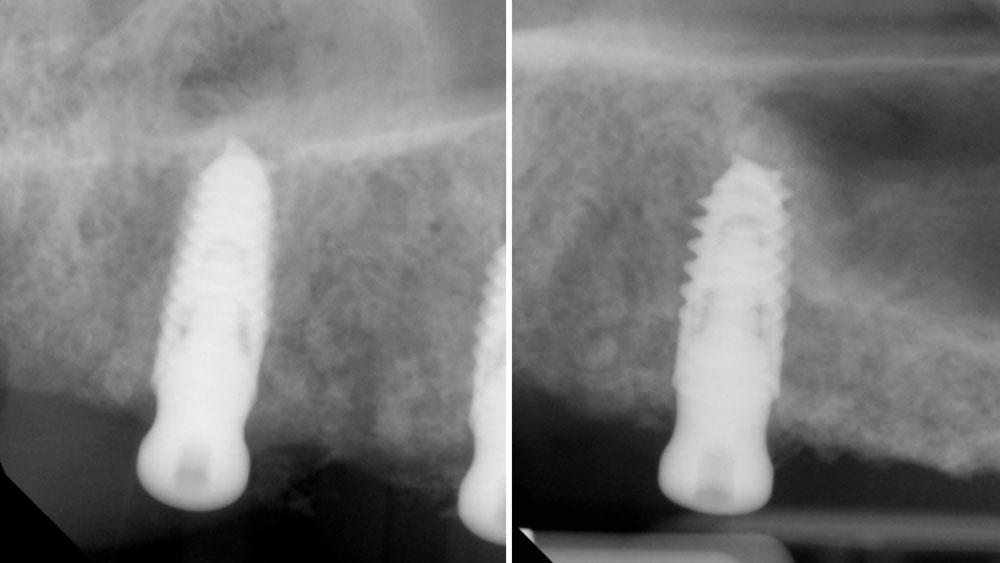

Horizontal (5–7 mm) and vertical (3–4 mm) ridge augmentation were successfully obtained, with stablewound management achieved through precise suturing techniques. The osteoinductive properties of the large vallos®, demineralized granules combined with rhPDGF-BB, a component of GEM21S® promoted high-quality bone regeneration, whereas the large Geistlich Bio‑Oss®, xenograft particles contributed to volume preservation by moderating resorption. As a result, four 4.3 mm implants were placed with high primary stability, each exceeding 35 N·cm of insertion torque, providing a strong foundation for a predictable esthetic and functional restoration.